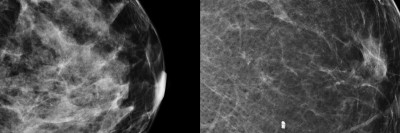

Dense breasts are normal. They have more fibrous or connective tissue. When you have a mammogram, the dense tissue looks white on the image of your breast. But cancer cells also look white on mammogram images. It can be hard to spot cancer cells in images of dense breasts.

Some people with dense breasts may need extra imaging tests, such as ultrasounds or MRIs, to help find any possible cancers.

You will know if you have dense breasts after getting a mammogram. In September 2024, the FDA ruled that breast density must be on your report after getting a mammogram. Having dense breasts can put you at a higher risk for breast cancer. Talk with your doctor about your risk.

MSK’s mammograms use tomosynthesis (toh-moh-SIN-thuh-sis), also called 3D mammography. It helps us see breast tissue and tumors more clearly. It’s helpful for people who have dense breasts. The pictures it takes are so detailed that most people will not need to come back for more images.